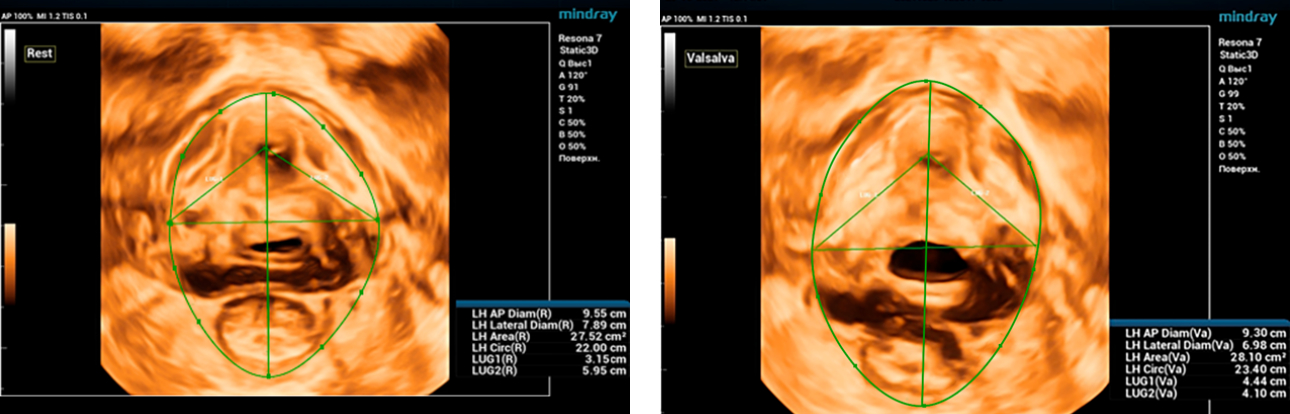

During ultrasound examination using Endocavity volume convex array transducer (DE10-3WU, Resona 7, Mindray), tearing of both levator ani muscles on the right and left is visualized, thinning of the tendon center of the perineum to 3-4 mm, the distance LH (levator hiatus) is increased ŌĆō 6.13 cm, LUG1 ( One side of the levator-urethra gap) ŌĆō 2.95 cm and LUG2 ŌĆō 3.15 cm (normally less than 2.5 cm)